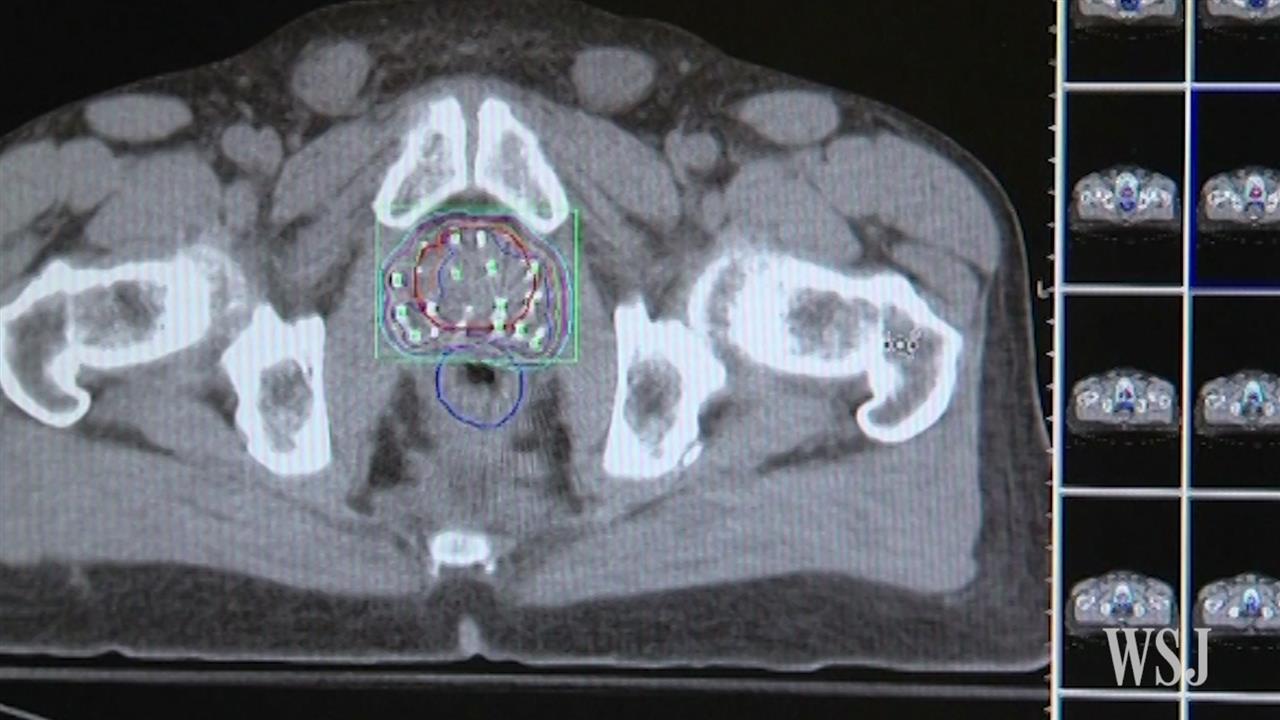

Prostate Cancer From Diagnosis To Death : Diagnostics | Free Full-Text | Review of Gallium-68 PSMA PET/CT Imaging

Prostate Cancer From Diagnosis To Death : Diagnostics | Free Full-Text | Review of Gallium-68 PSMA PET/CT Imaging. Compared to established threshold values, men with mpc reported poor qol and functioning particularly in the last few months before death, and a . Rate of new cases and deaths per 100,000: If you or someone you know has been diagnosed with ovarian cancer, learn all the essential information needed to understand this condition and what to expect from treatment. Prostate cancer is the second leading cause of cancer death in american men, behind only lung cancer. It is estimated that 34,500 deaths from this disease will occur in the .